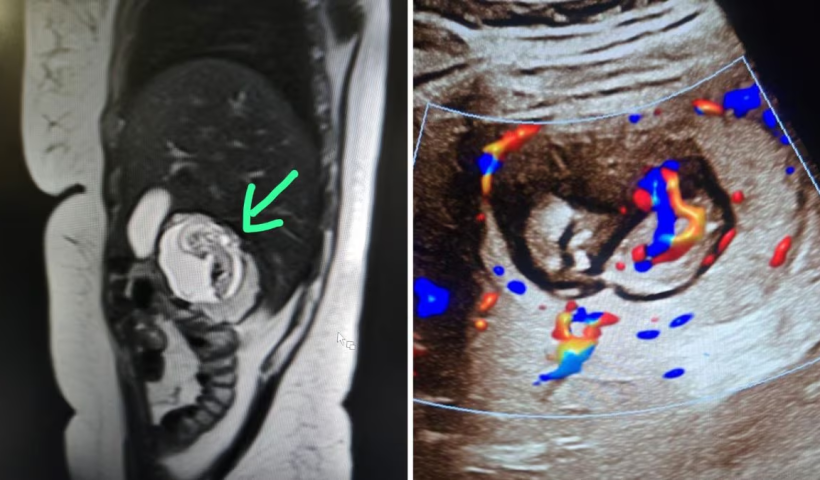

உத்தரப்பிரதேச மாநிலம் புலந்த்சாகரில் நடந்த ஒரு அசாதாரண மருத்துவ சம்பவம், மருத்துவ உலகையே வியப்பில் ஆழ்த்தியுள்ளது. 30 வயது பெண் ஒருவருக்கு எடுக்கப்பட்ட எம்.ஆர்.ஐ. ஸ்கேனில், அவர் 12 வார கர்ப்பமாக இருப்பதும், ஆனால்…

View More கருப்பையில் வளராமல் கல்லீரலில் வளரும் கரு.. இந்தியாவில் இதுதான் முதல் முறை.. உபி கர்ப்பிணிக்கு ஏற்பட்ட சிக்கல்.. என்ன செய்ய போகிறார்கள் மருத்துவர்கள்?